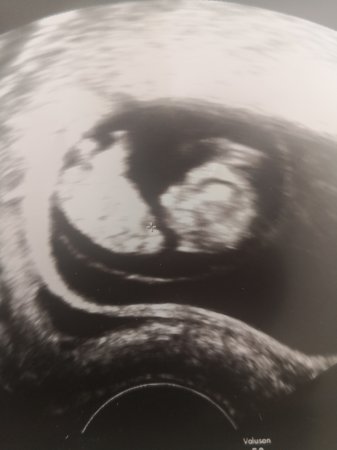

Så fin. Ser allerede ansiktstrekkCa ti uker. Armer, bein, hjerte og hjerne på plassVis vedlegget 302667

NomminCa ti uker. Armer, bein, hjerte og hjerne på plassVis vedlegget 302667